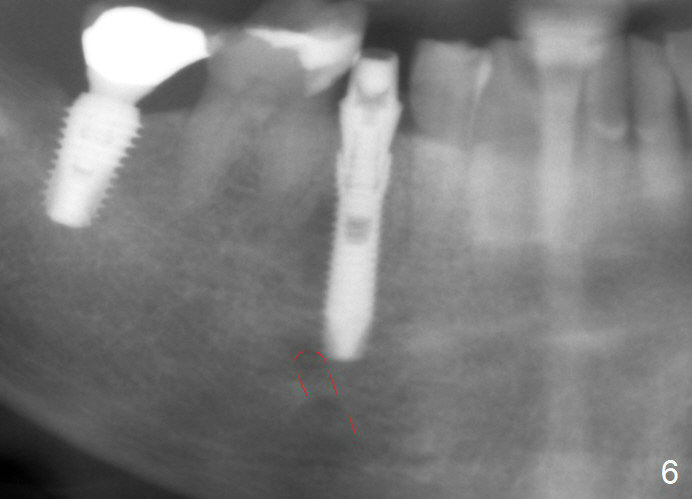

A 67-year-old woman fractures the tooth #29 three months post RCT. There is persistent periapical radio-lucency (Fig.1 yellow dashed line), which is close to the Mental Loop (red dashed line). Since the root of the affected tooth deviates distal, osteotomy will be established mesial (Fig.2). In fact it is not so easily accomplished; the osteotomy is initiated as mesial as possible (Fig.3 (yellow dashed line: original socket)). When a 3.8x16 mm implant is being placed, it is distal (Fig.4). The MO composite of the tooth #30 has to be trimmed for fabrication of an immediate provisional (Fig.5 <).

To reduce the chance to injury the buccally located loop, the osteotomy should be as lingual as possible. Initial depth is 19 mm (gingival level, Fig.3). In fact all of the three intraop PAs (Fig.3-5) do not show the Mental Loop until panoramic X-ray is taken immediately postop (Fig.6). There is no postop paresthesia. There appears no gap around the implant 3.5 months postop (Fig.7 >).